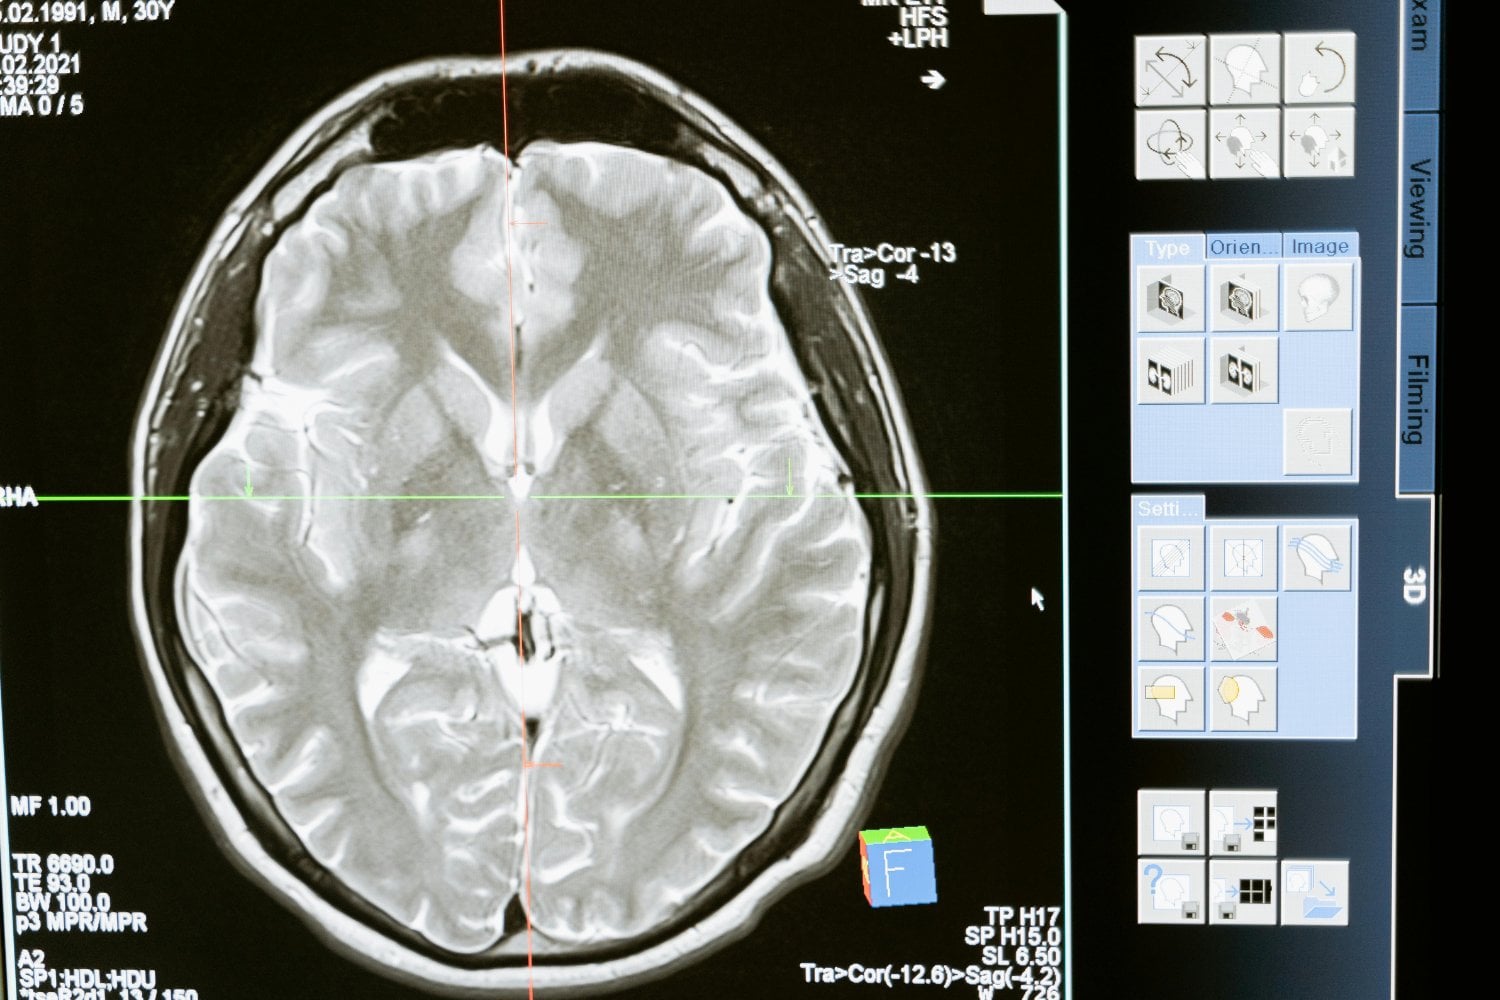

El avance se basa en implantar diminutas matrices de electrodos en la corteza motora, donde se originan las órdenes hacia los músculos del habla. Aunque la boca y la lengua no se muevan, el cerebro sigue emitiendo señales eléctricas.

Los algoritmos de aprendizaje automático analizan estas señales y reconstruyen palabras probables a partir de fonemas básicos. Así, un patrón que corresponde a los sonidos “D” y “G” puede identificarse como la palabra dog (“perro”).